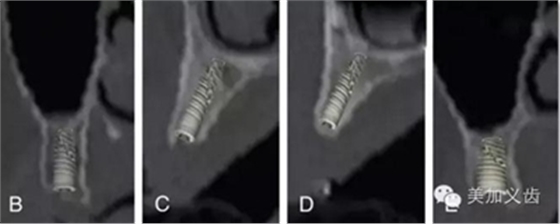

——錐形束CT

這個是三維放射線重建影像可以全面、準確的評價解剖學結(jié)構(gòu),包括可用骨形態(tài)的三維數(shù)值,通俗點講就是可以看到可用骨的垂直向、近遠中向和頰舌向的數(shù)值。

其優(yōu)點是:可以提供精確的、亞毫米級測量數(shù)值,與印模結(jié)合,通過CBCT數(shù)據(jù)來實現(xiàn)模擬手術并制作外科導板。CBCT的放射量與傳統(tǒng)CT相比要小很多,放射時間短,操作也比較簡單。

現(xiàn)在很多廠家都能夠制作外科導板了,醫(yī)生把CBCT數(shù)據(jù)和石膏模型發(fā)送給加工廠,加工廠通過軟件設計來進行虛擬種植,就能通過3D打印技術或者CAD/CAM做出手術導板。你不用管他們是怎么做的,總之你能得到一個手術導板,有了導板的幫助,種植手術的難度會降低很多,尤其是多顆牙的種植手術。

其缺點是:設備成本還是比較高,分辨率略顯不足,而且會存在一定程度上的影像學偽影。